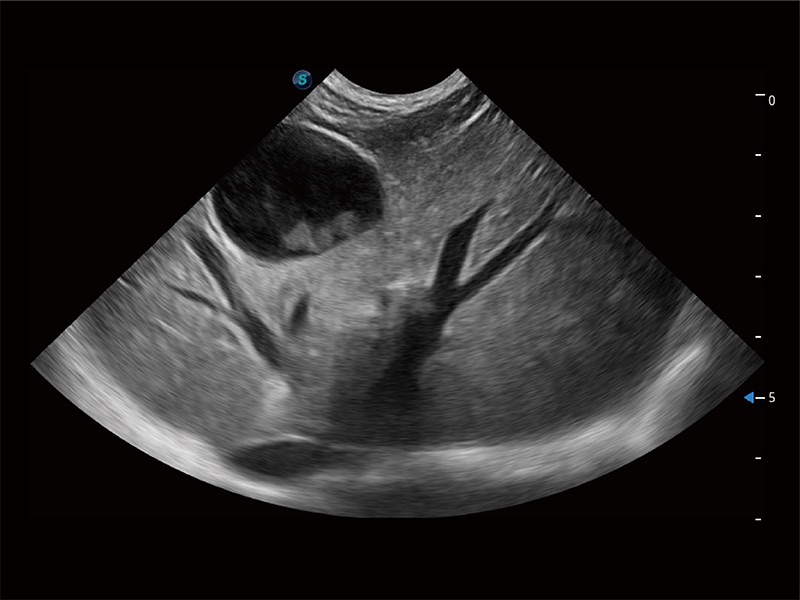

ProPet 80 全新的動物超聲智能軟件和豐富的探頭群,為動物醫(yī)生提供了高清晰度和精細分辨率的圖像,無論在寵物、馬科、畜牧還是實驗室動物等應(yīng)用中都可以輕松應(yīng)對,為您的日常工作帶來滿意的體驗。

高性能和先進的臨床應(yīng)用工具可以為動物醫(yī)生提供臨床信心。ProPet 80 搭載了先進的腹部和淺表應(yīng)用工具,幫助醫(yī)生在日常臨床實踐中發(fā)揮前所未有的作用。

為精細結(jié)構(gòu)及組織邊緣提供高清晰度的圖像和更大的成像視野。幫助減輕醫(yī)生的用眼疲勞,快速精準獲得測量的數(shù)據(jù)。